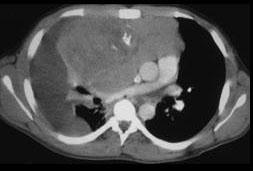

女,34岁,咳嗽,咯血半月余,请结合影像学检查,选出最可能的诊断 ( )A、神经源性肿瘤B、肺癌C、淋巴瘤D、胸腺瘤E、纵隔畸胎瘤

问题 女,34岁,咳嗽,咯血半月余,请结合影像学检查,选出最可能的诊断 ( )

选项 A、神经源性肿瘤 B、肺癌 C、淋巴瘤 D、胸腺瘤 E、纵隔畸胎瘤

答案 E